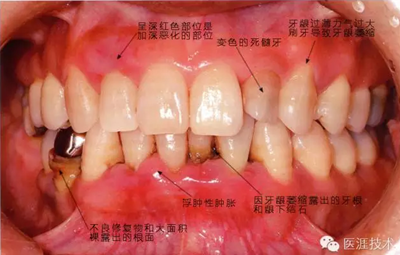

患有牙周病的牙周組織的臨床照片

56歲牙周炎男性的臨床照片

正在服用高血壓藥中的56歲男性。菌斑控制得不好。通過牙周探診,全頜有4~6mm的牙周袋,在X光片中可以看到全頜中度牙槽骨吸收,磨牙處一個地方是重度牙槽骨吸收。通過比較牙周病進(jìn)展?fàn)顟B(tài),邊緣部有大范圍浮腫(發(fā)紅、腫脹),和纖維性肥厚。這也可能是服用中的降壓藥的副作用導(dǎo)致的。因?yàn)檠例l、牙槽骨比較厚,牙齦呈架子狀。